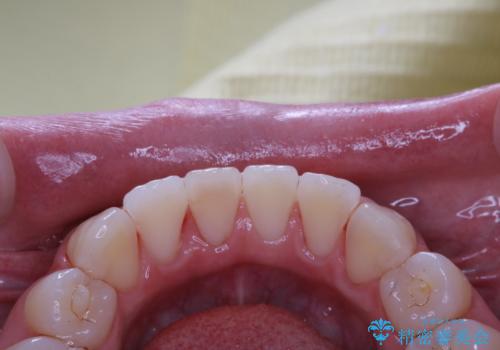

1年ぶりにPMTCで歯の着色落とし

- しばらく歯科医院へ行けなかったため、しっかり着色や汚れを落として欲しいとのことで来院されました。全体的に着色や歯石が付着していたためPMTC60分コースを行いました。